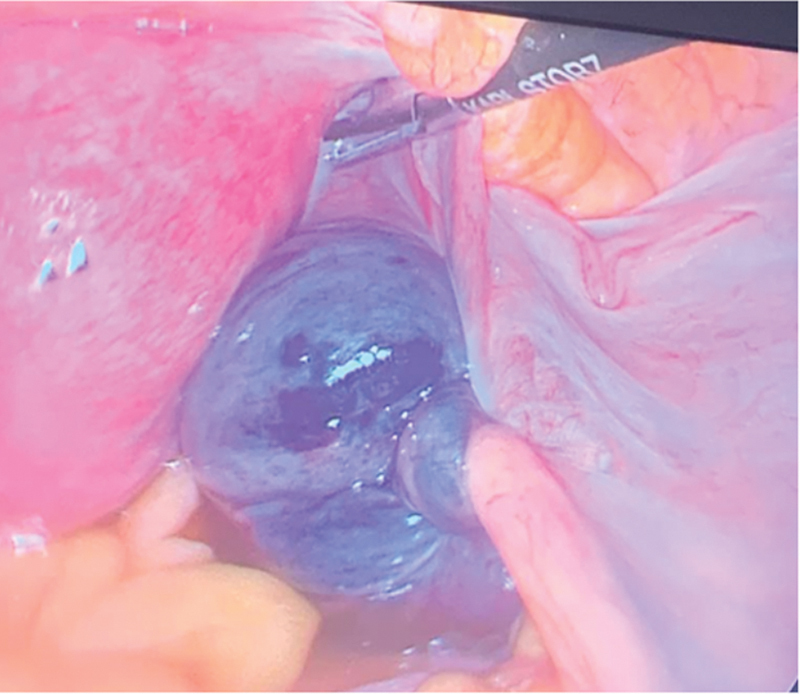

卵巢扭转是妇科急症之一,手术治疗是挽救卵巢的标准方法,同时也能发现一些意外的解剖缺陷,这些缺陷会增加卵巢扭转的风险。我们报告了一例因怀疑卵巢扭转而接受腹腔镜诊断的 27 岁单身女性病例。术中,我们发现右侧附件扭转(卵巢和输卵管),右侧卵巢和输卵管嵌顿在位于右侧子宫骶骨韧带内侧的大腹膜囊中。使用非创伤性腹腔镜镊子将肿胀的附件剥离并小心拉至大腹膜囊外侧。左侧附件正常。患者进行了第二次腹腔镜检查,计划对大腹膜缺损进行腹膜闭合。以前曾有两例报告过卵巢嵌顿,但与卵巢扭转无关,也不涉及腹膜闭合,与我们报告的卵巢剥离和腹膜缺损闭合不同。这种情况的病因可能是先天性的,因为没有其他明显的病因,如盆腔创伤、既往手术、盆腔炎或子宫内膜异位症。我们的临床评估表明,腹膜囊可以防止卵巢自发剥离,从而加强卵巢扭转的进程,使其在被困在腹膜囊中时发生缺血性病变。这种情况会导致囊壁之间的细胞受压,随后组织水肿,从而增强缺血效应。

Ovarian torsion is one of the gynecological emergencies and surgical intervention is the standard management for ovarian salvage as well as reveals some unexpected anatomical defects that increase the risk of ovarian torsion. We report a case of a 27-year-old single, nulliparous female taken for diagnostic laparoscopy with suspicion of ovarian torsion. Intraoperatively, we found right adnexa torsion (ovary with tube) along with incarceration of the right ovary and tube into the big peritoneal sac, which was located medial to the right uterosacral ligament. Detorsion and careful pulling of the swollen adnexa were done to the outside of the big peritoneal sac using nontraumatic laparoscopic forceps. The left side was normal with normal left adnexa. The patient had a second laparoscopic look with a plan for peritoneal closure of the big peritoneal defect. There are two cases which have previously reported ovarian incarceration, but were not associated with ovarian torsion, and did not involve peritoneal closure unlike our report of ovarian detorsion and peritoneal defect closure. The etiology of this condition is thought to be likely congenital as there were no other visible etiologies like pelvic trauma, previous surgery, pelvic inflammatory disease, or endometriosis. Our clinical assessment suggests that a peritoneal sac can enhance the course of ovarian torsion to involve ischemic changes of the ovary when trapped inside of it, by its prevention of spontaneous detorsion. This condition will result in the compression of the cells between the sac wall and subsequent tissue edema enhancing the ischemic effect.